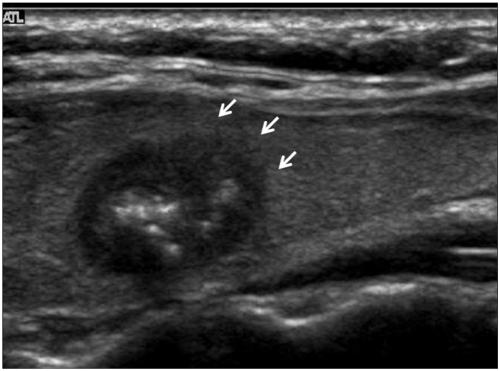

The common US findings for MTCs were solid internal content (91%), an ovoid to round shape (57%), marked hypoechogenicity (52%) and calcifications (52%). Among the 21 cases of MTC nodules, 17 (81%) were classified as suspicious malignant nodules. The mean size (longest diameter) of MTC nodules was 19 +/- 13.9 mm and the mean size (longest diameter) of PTC nodules was 11 +/- 7.4 mm; this difference was statistically significant (p < 0.05). An ovoid to round shape was more prevalent for MTC lesions than for PTC lesions (p < 0.05).

MTC常见的US表现为内部实性成分(91%)、卵圆形至圆形(57%)、明显低回声(52%)和钙化(52%)。在21例MTC结节中,17例(81%)被分类为可疑恶性结节。MTC结节的平均大小(最长直径)为19±13.9mm,PTC结节的平均大小(最长直径)为11±7.4mm;这种差异具有统计学意义(p<0.05)。MTC病变中卵圆形至圆形比PTC病变更常见(p<0.05)。